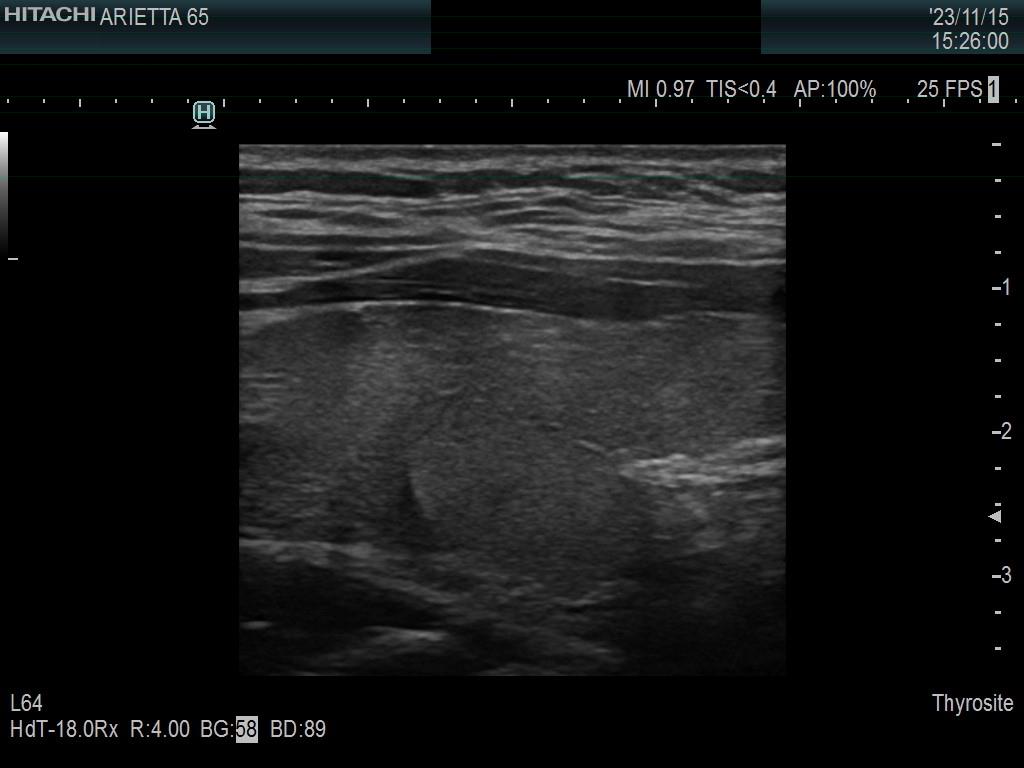

Introduction - case 1407 (ultrasonographic picture 11)

Left lobe, longitudinal scan. Two circumstances explain that at first sight we can judge the dorsal part of the lobe as a nodule. The fragmented connective tissue running ventral and the hypoechoic areas upper and lower (i.e. left and right in the image) to this part of the lobe.